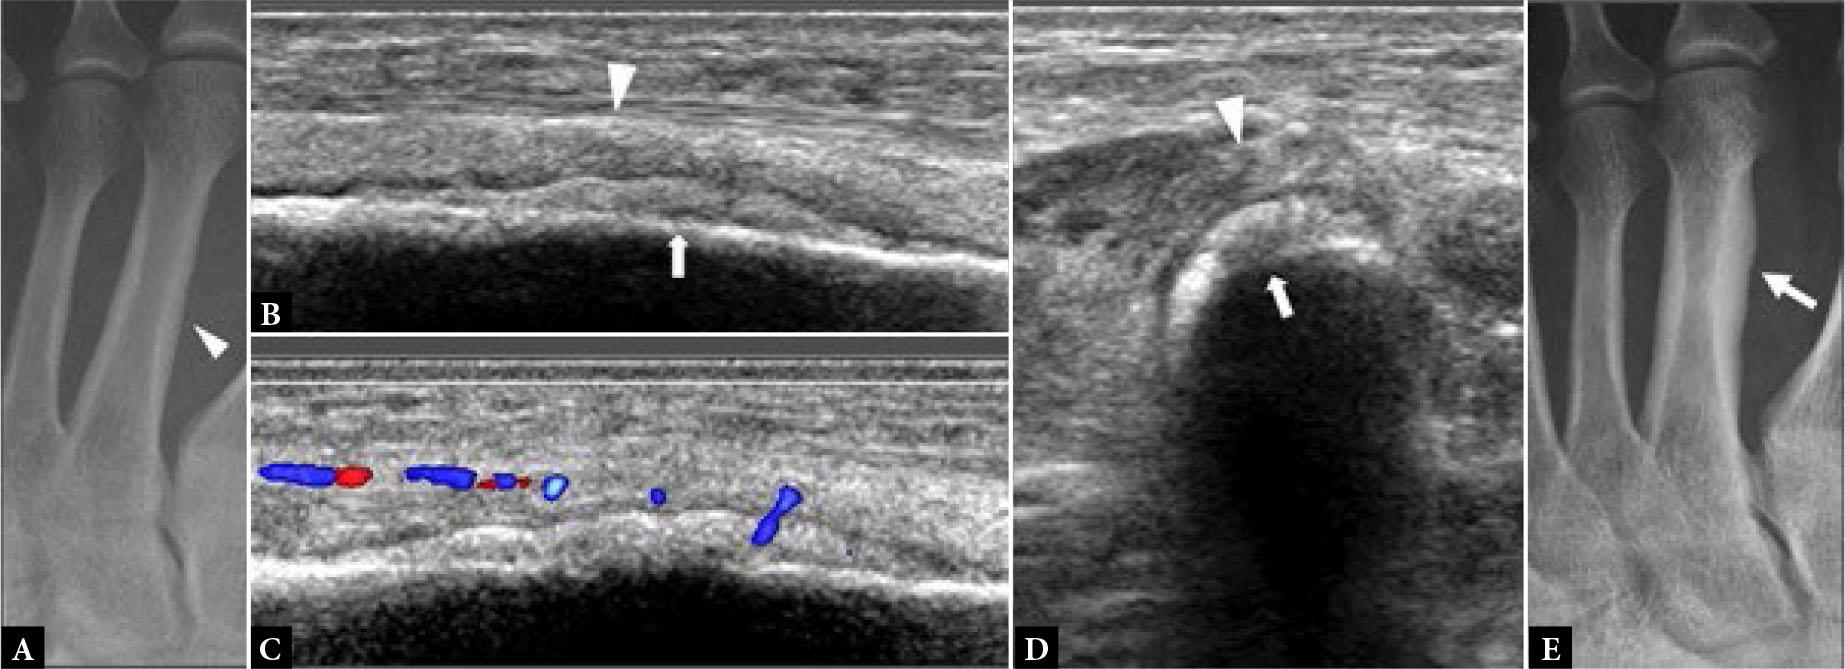

Fig. 1.

41-year-old female with forefoot pain and swelling for one month. There was no specific traumatic event and no undue sporting activity. A tendon injury was suspected clinically A. Dorsoplantar (DP) radiograph shows normal 2nd metatarsal bone (arrowhead). B. Longitudinal greyscale and C. color Doppler, and D. transverse greyscale US images show moderate severity localized periosteal thickening (open arrow) of the 2nd metatarsal shaft dorsally, with moderate adjacent soft tissue thickening (open arrowhead) consistent with active stress fracture. E. Radiograph three months later showed marked periosteal thickening of the 2nd metatarsal shaft (arrow) compatible with healed stress fracture